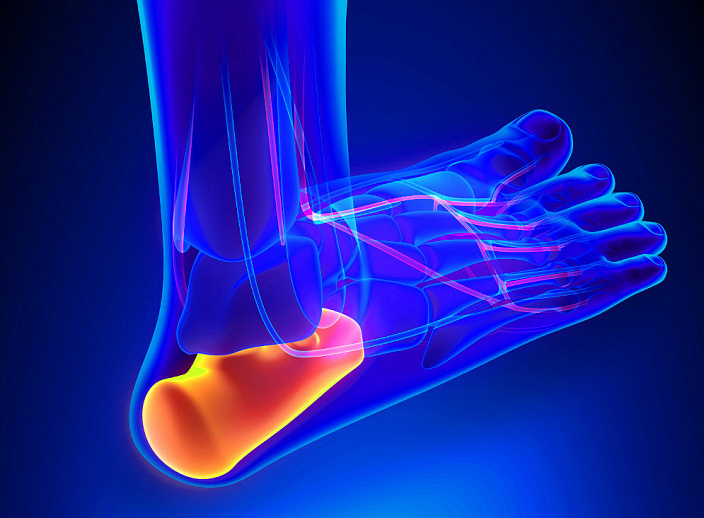

Самый уязвимый сустав в человеческом скелете – голеностопный. Это место, где находится лодыжка, именно с его помощью соединяется кость на ноге над ступней с таранной и пяточной. В его состав входит система костей, связки и мышцы.

В отверстие между большой и малой берцовой костью входит отросток кости стопы. Вокруг этого соединения и формируется сустав. Кости голеностопного сустава распределяют давление веса человека на стопу.

Движение в суставе происходит за счет мышц и связок. Связки фиксируют кости сустава на своих местах в анатомически правильном положении. Они объединены в одну общую систему.